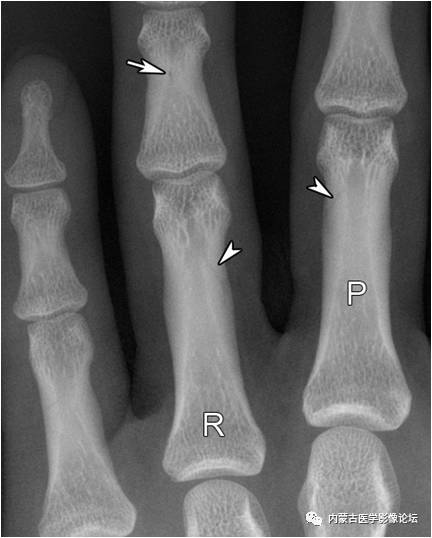

指骨滋养血管:箭头所示斜行透亮线影为近节指骨滋养血管,而白箭所示小圆形透亮区为中节指骨滋养血管轴位投照所致。注意指骨滋养血管从近端斜向远端,从骨皮质斜行走向髓腔,与掌骨相反。R:环指,P:近节指骨。

指骨Mach效应:箭头所示为环指(R)与小指骨结构内的软组织重叠影所形成的Mach效应,其走行与滋养血管影相反,也不应误为骨折线。

指骨正常骨突与骨嵴:白箭所示为肌腱附着的骨突与骨嵴,不应误为骨痂或骨膜增生。R:环指,P:近节指骨,M:中节指骨,D:远节指骨。